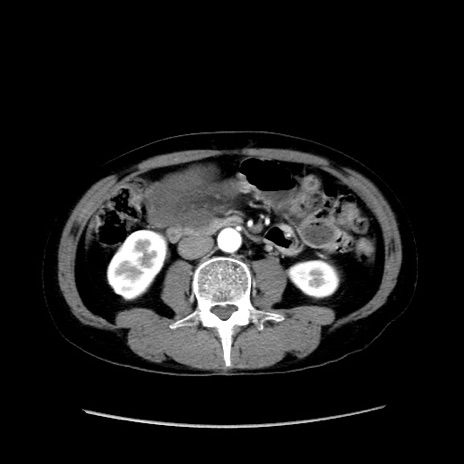

冠状断像

症例37(横断像)

【症例】40歳代 男性

【主訴】腹痛

【現病歴】4時間ほど前に電車に乗車中に臍部上より腹痛出現。徐々に増悪し起立困難となり、救急外来受診。生ものは数日食べていない。今朝お雑煮を食べた。

【身体所見】BT 36.8℃、BP 117/84mmHg、HR 91/min、SpO2 97%、苦悶様、腹部:臍上部広範囲圧痛あり、反跳痛±

【データ】WBC 8100、CRP 0.03